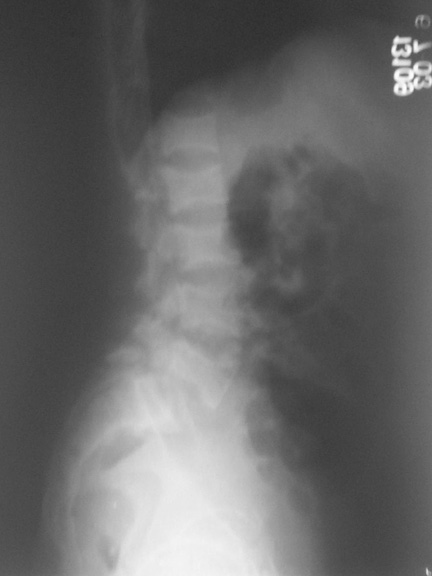

This patient,a middle aged malewas a diagnosed case of hypophosphatemic osteomalacia on treatment. Unfortunately he discontinued treatment since he was poor and also neutral phosphate was not available locally. He presented with pathological fracture of left femur and a failing neck of same femur.

We managed to get neutral phosphate, initiated medical treatment and did an antegrade SIGN nailing of left femur along with couple of screws to neck using miss a nail technique. He complained of pain of the right femur and both forearms. In OT these areas were screened using image intensifier and found that he has looser zones of all these with impending fractures. Yesterday we did a retrograde nailing of right femur usingSIGN nail. Both ulnas were stabilised usingLambrudini wires in a closed fashion. All fractures and looser zones were stabilised by closed surgery using image intensifier. It may be interesting to see the post of picture of both the hips in which one side shows an antegrade femoral SIGN nail and the other side shows a retrograde SIGN nail.